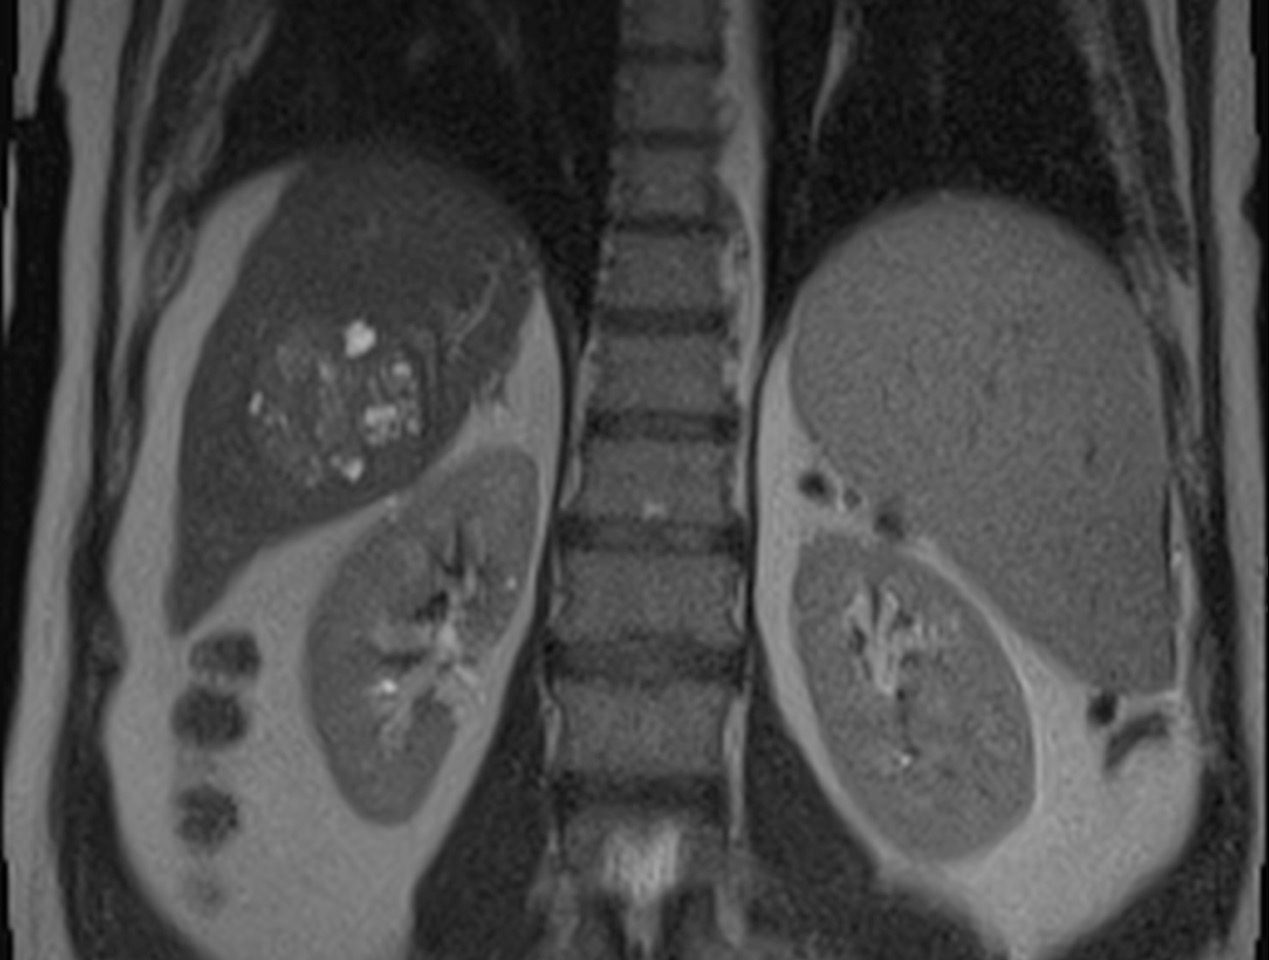

Cel mai tare Nou Rmn Ul Abdominal Pelvin Cu Protocol De EndometriozÄ La Centrul De Radiologie Èi ImagisticÄ Dorna Medical Vatra Dornei Dorna Medical